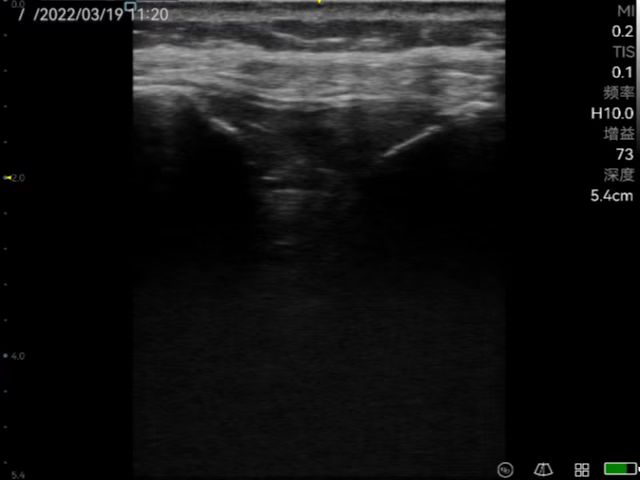

Musculoskeletal ultrasound technology (referred to as musculoskeletal ultrasound) has developed rapidly domestically, and has been continuously promoted and applied in clinical practice. It has become the first choice or gold standard in the diagnosis and treatment of many diseases, such as peripheral nerve diseases, muscle and tendon acute and chronic diseases, early diagnosis and differential diagnosis of rheumatism and rheumatoid diseases. Rehabilitation medicine has developed rapidly in recent years. With the aging of the population, the development of the hierarchical diagnosis and treatment system, and the emergence of precision medicine, medical imaging, especially ultrasound medicine, plays a very important role in rehabilitation medicine. At present, rehabilitation medicine in our country relies on traditional physical examinations, and its blindness, randomness, untargetedness and lack of objective indicators for judging efficacy have attracted more and more attention. Musculoskeletal ultrasound has the advantages of non-invasiveness, convenience and practicality which can be used as the first-choice imaging examination for rehabilitation medicine. Ultrasound positioning and ultrasound-guided puncture injection technology have become the "third eye" of rehabilitation physicians which has an irreplaceable role in manipulative therapy, rehabilitation equipment therapy, injection therapy and sports rehabilitation, etc.

Peri-articular injection to help diagnose and guide injection of anti-inflammatory drugs for frozen shoulder.

Application in joint ultrasound (wrist, shoulder, elbow, hip, knee, ankle, etc.); Therapeutic application of muscle, tendon, myofascial pain syndrome; Application in urinary system rehabilitation; Application of ultrasound-guided botulinum toxin injection therapy; Applications of Neurosonography; Applications of Cardiac Ultrasound; Application of interventional ultrasound (interventional treatment of joint disease, cystic disease); Expanded application of ultrasound in traditional medicine (ultrasound visualization acupotomy technology); Application of pelvic floor ultrasound in rehabilitation of diseases; Application of ultrasound-guided puncture in pain.